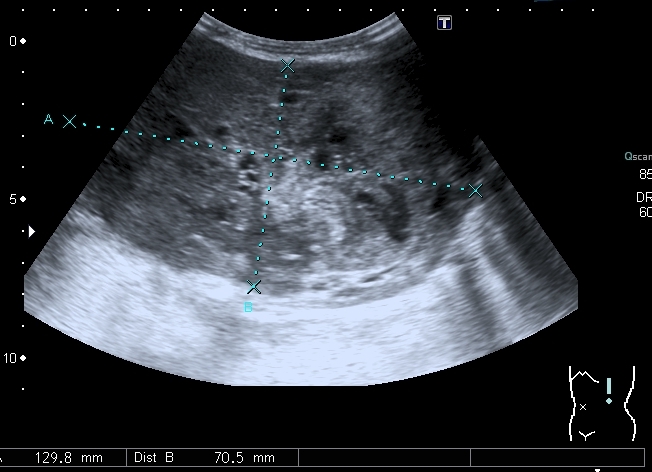

Предлагаю интересные изображения, полученные при сканировании лёгких через межрёберные промежутки и печень у ребёнка 4-х лет с подозрением на пневмонию

участок безвоздушной легочной ткани....похож на печень...пневмония в стадии опеченения... ;)

Согласен в отношении нижней доли правого лёгкого, изменения в ней похожи на сливную инфильтрацию при пневмонии, хотя носят несколько многоузловой характер. Но то что мы видим со спины в левом лёгком на пневмоническую инфильтрацию не похоже.